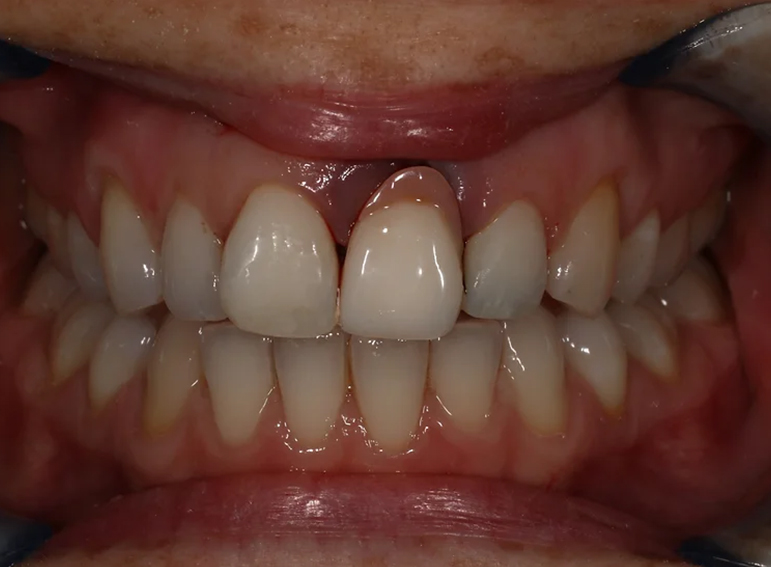

External cervical resorption extracted with a temporary adhesive bridge and final adhesive bridge.